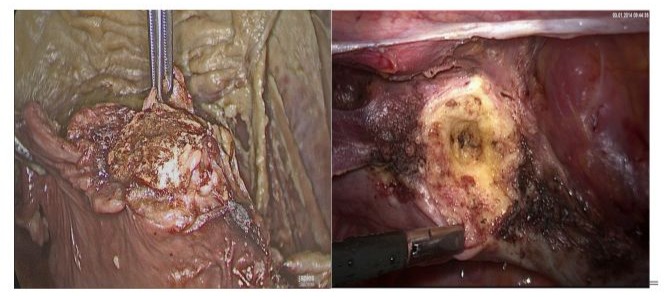

Only with good knowledge of “clinical anatomy” endoscopic surgical procedures (Figure 1) can be understood. The training of laparoscopic surgery on body donors definitely enriches all learning efforts (Figures 2 and 3). When teaching on body donors there is no time pressure, which - of course - at life surgical demonstrations has to be discussed. Figure 4 shows the final surgical situation after SLH (Subtotal Laparoscopic Hysterectomy) performed in a body donor compared to a patient.

Figure 4: Cervical stump after a body donor Laparoscopic Subtotal Hysterectomy (LSH) (4a) in comparison to a patient LSH (4b)